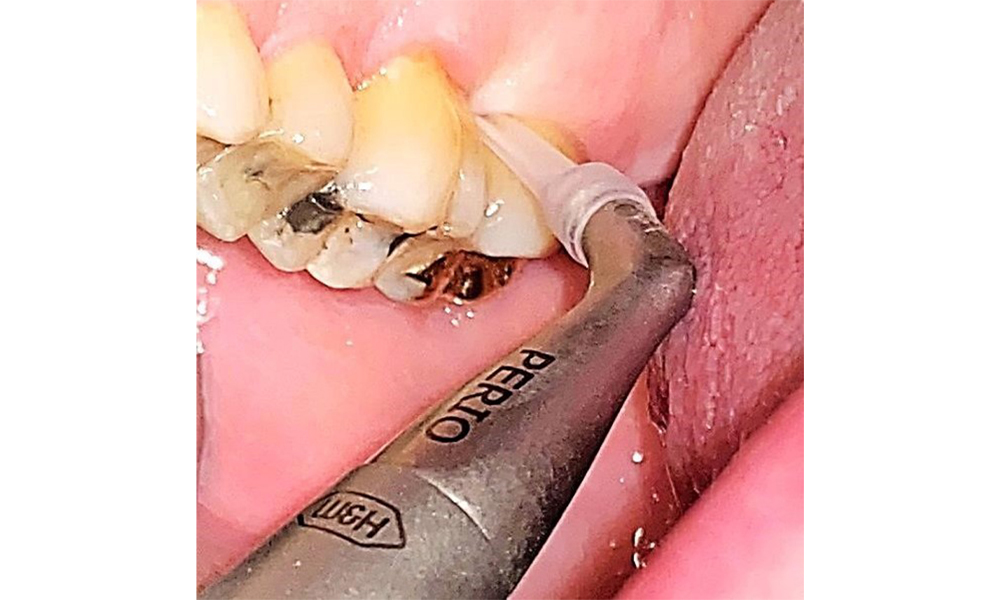

In der Instrumentierung sind bezüglich der Methodenwahl keine Einschränkungen gegeben. Aufgrund der parodontalen Vorerkrankung und dem hohen Rezidivrisikos ist die Vorbeugung einer Erkrankungsprogression durch die regelmäßige supra- und subgingivale Instrumentierung unerlässlich. Die Wahl der Instrumente zur mechanischen Biofilmentfernung ist aus allgemeingesundheitlicher Sicht nicht eingeschränkt und erfolgt bedarfsgerecht. Harte und mineralisierte Beläge wie Zahnstein und Konkremente sind mittels Handinstrumenten oder Schall/ Ultraschallscalern zu entfernen (Abb. 9) (8, 9).

Anwendung einer Ultraschallspitze zur Entfernung von harten mineralisierten Belägen (hier Proxeo Ultra mit Perio Spitze, W&H). © Dr. R. Krapf

Abb. 9: Anwendung einer Ultraschallspitze zur Entfernung von harten mineralisierten Belägen (hier Proxeo Ultra mit Perio Spitze, W&H). © Dr. R. Krapf